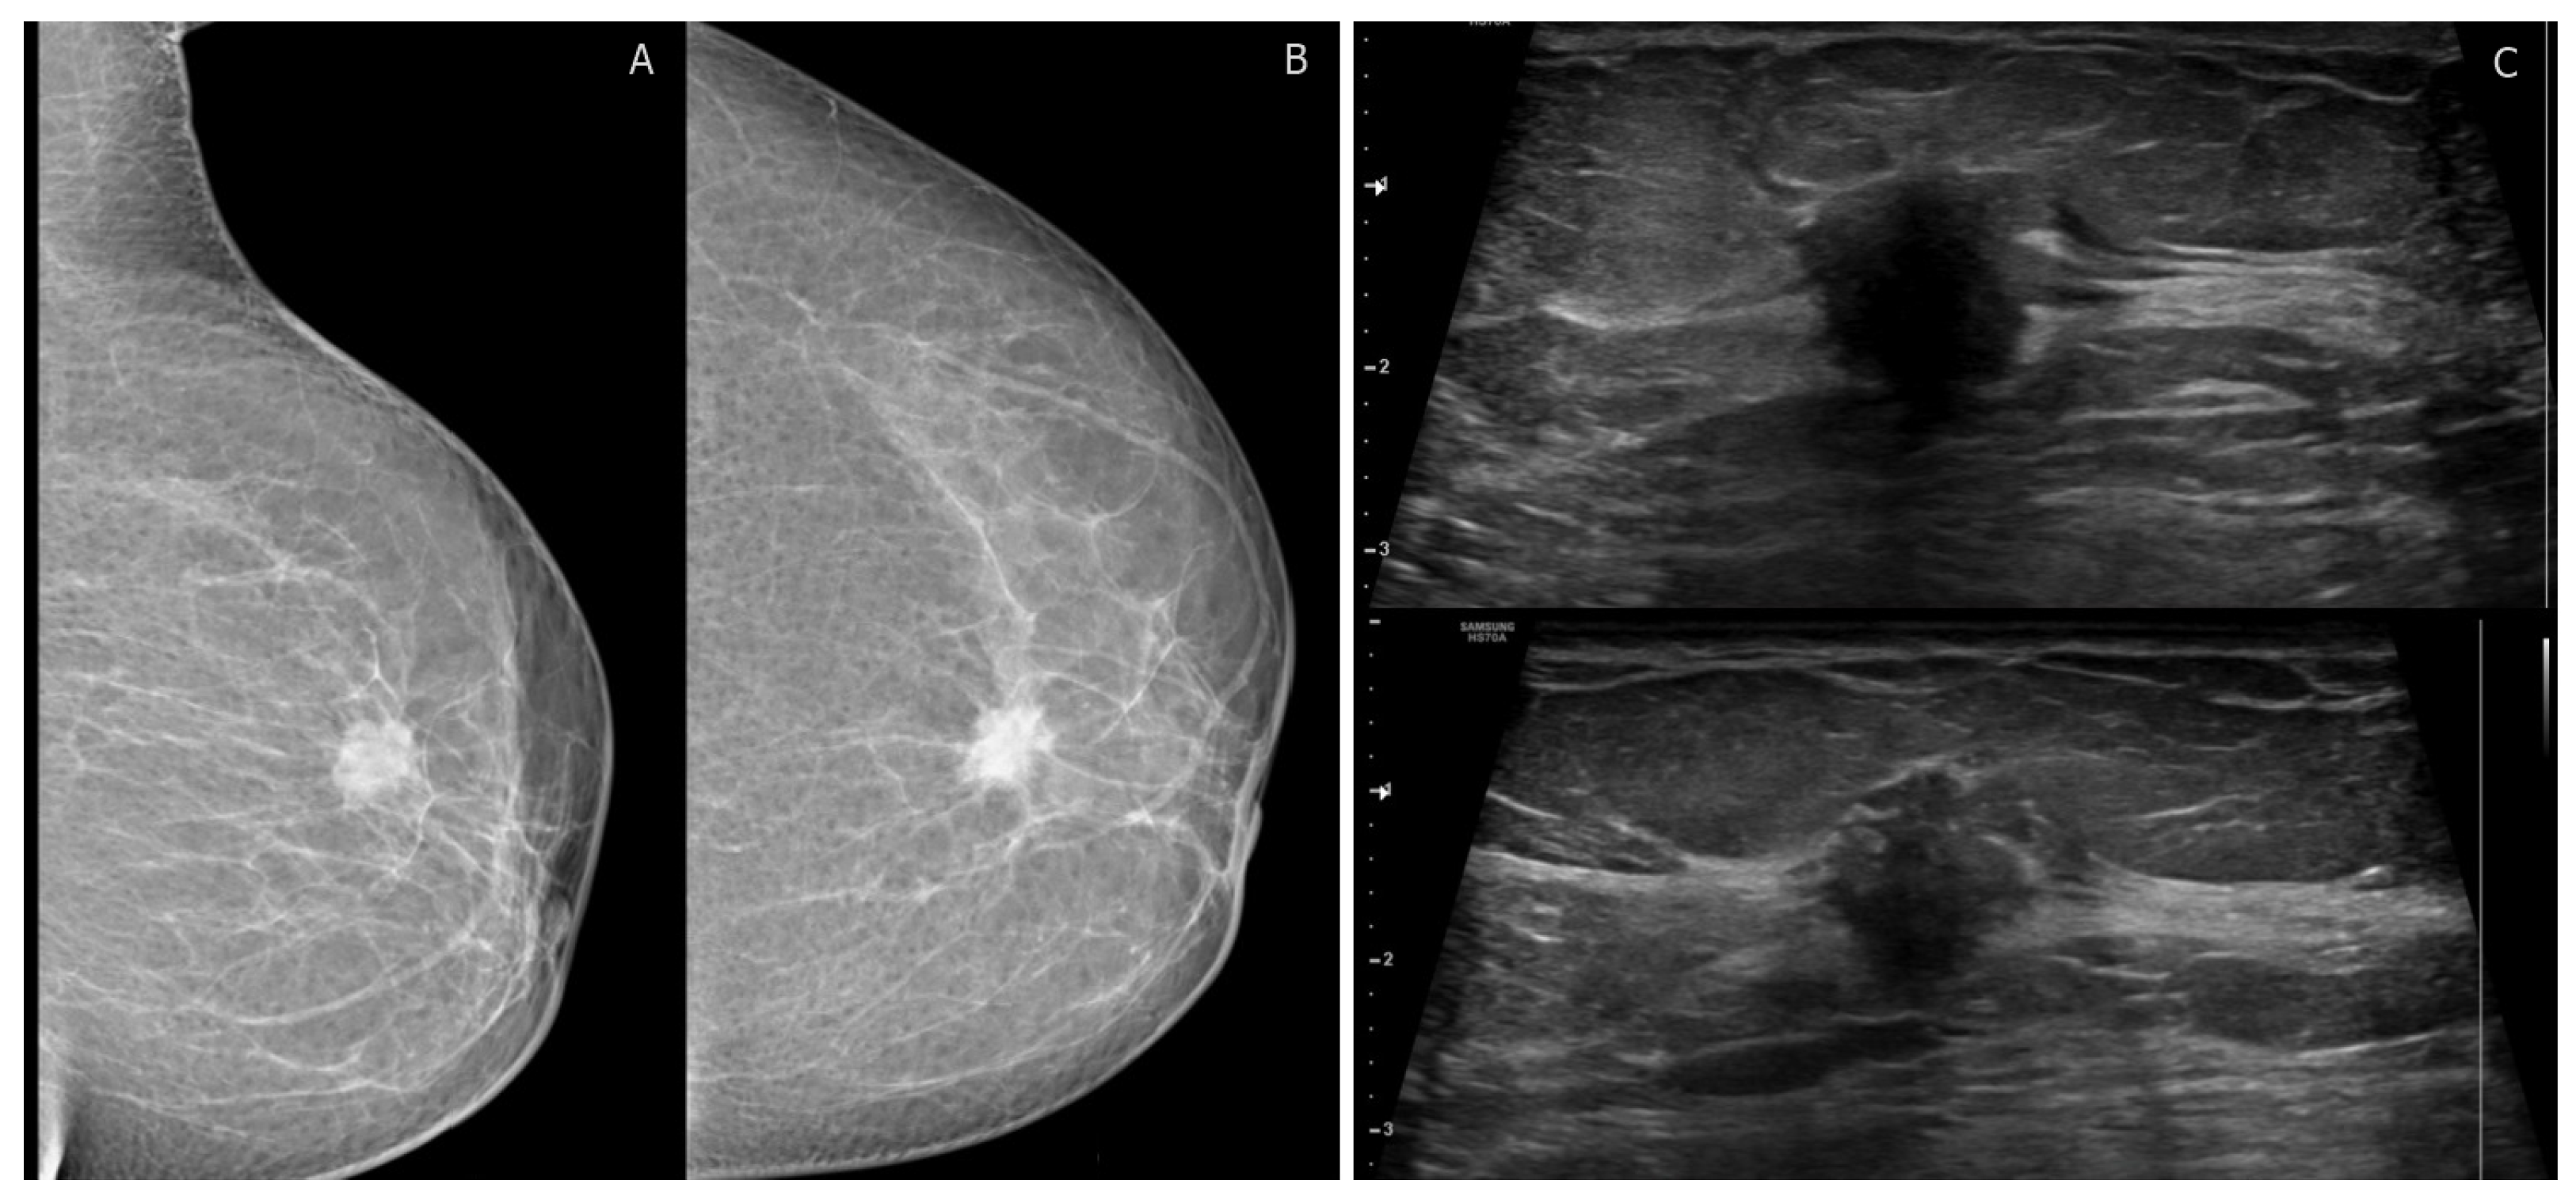

Figure 1.

BI-RADS category 4C: 40-year-old woman with invasive ductal carcinoma. (A,B) left mediolateral oblique and craniocaudal digital mammogram show irregular high-density mass with spiculated margins. (C) transverse ultrasound shows an irregular mass with angular margins and posterior shadowing corresponding to mammographic findings. No suspicious axillary LNs.